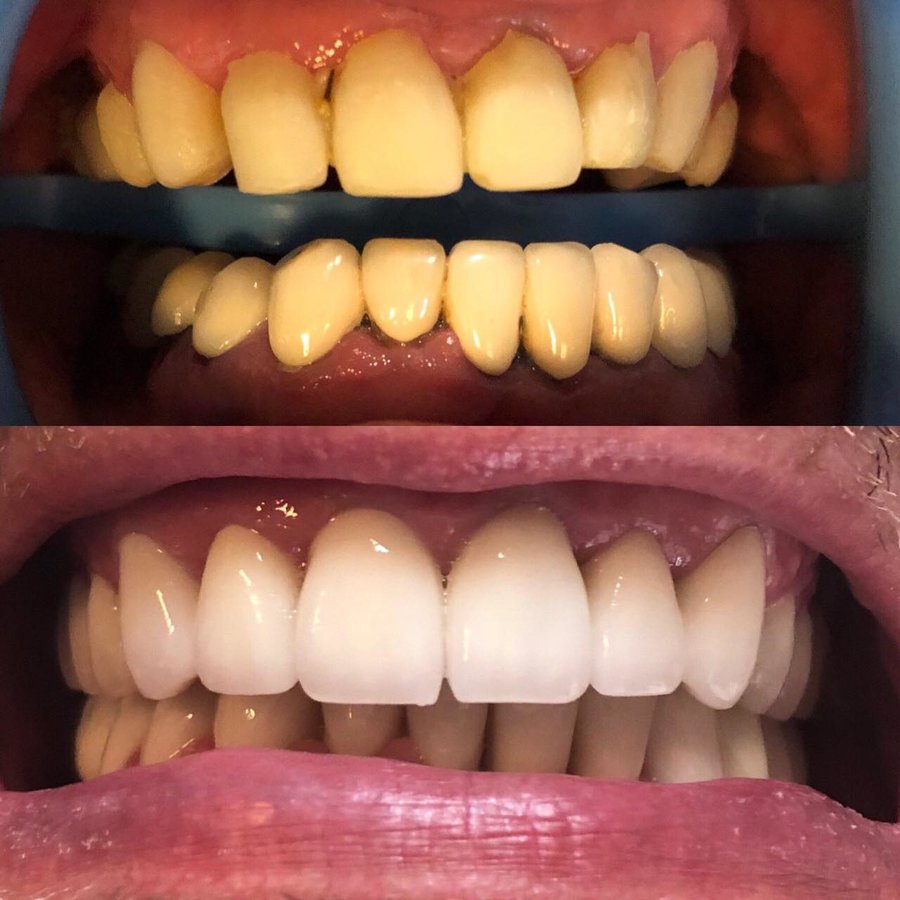

Veneers $334

Dental Crowns $139